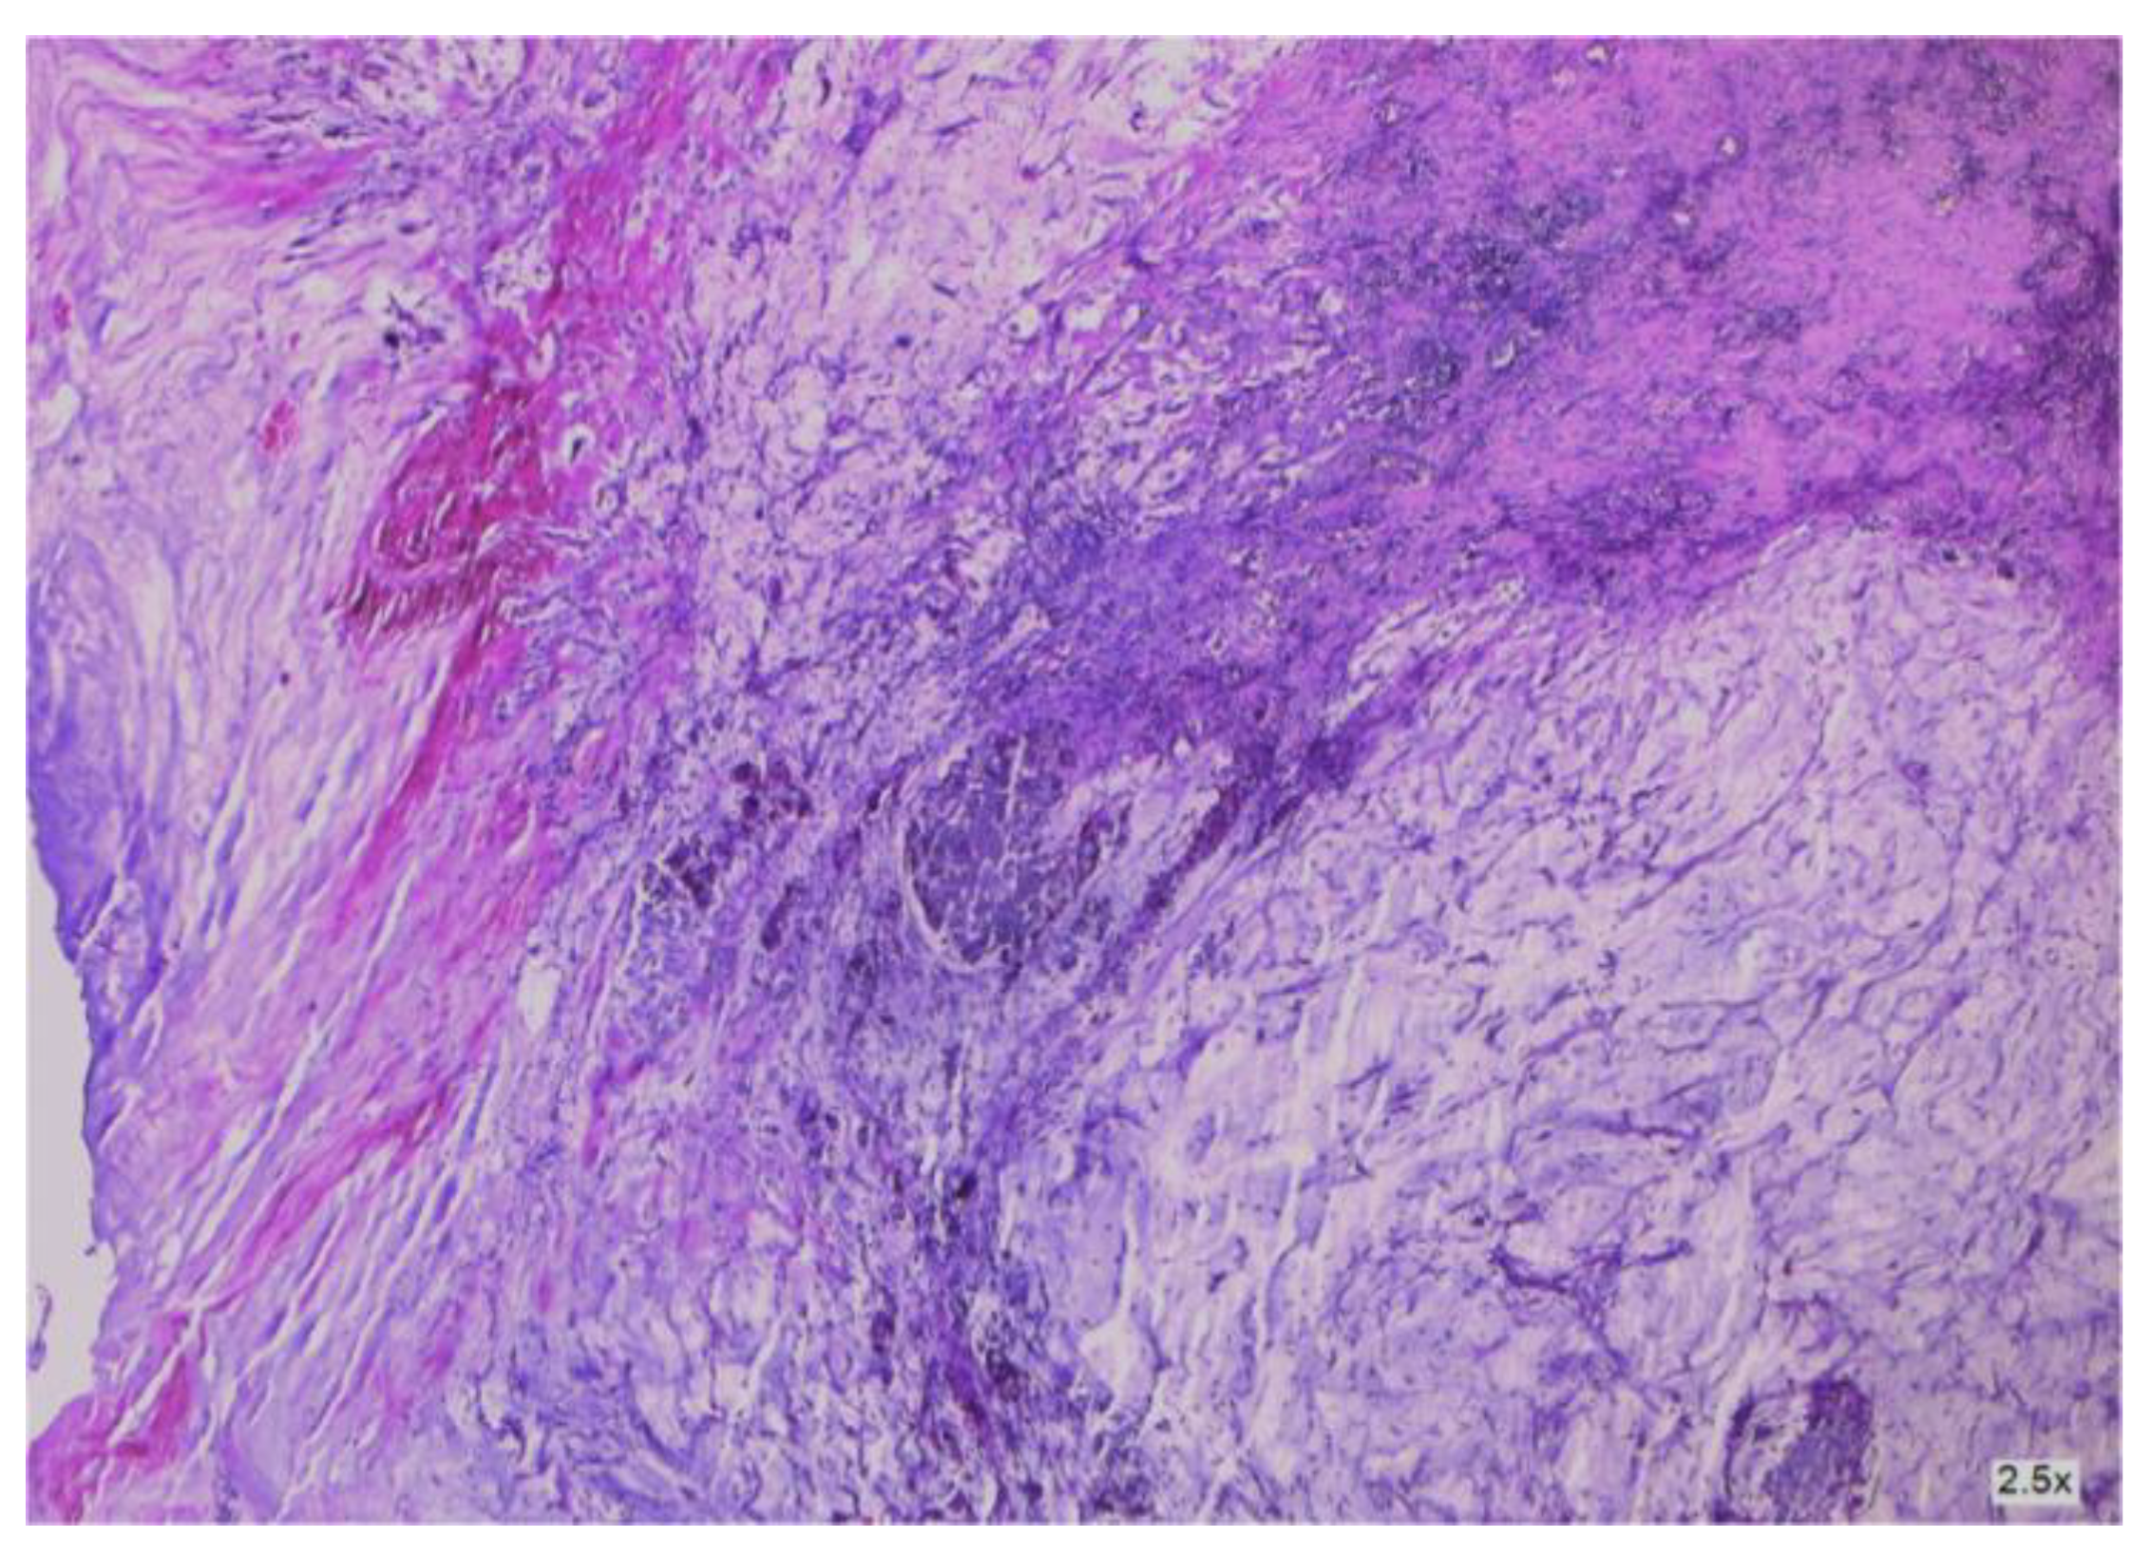

3.2.2. Clinical and Pathology Findings

- Dundr, P.; Singh, N.; Nožičková, B.; Němejcová, K.; Bártů, M.; Stružinská, I. Primary mucinous ovarian tumors vs. ovarian metastases from gastrointestinal tract, pancreas and biliary tree: A review of current problematics. Diagn. Pathol. 2021, 16, 20. [Google Scholar] [CrossRef] [PubMed]